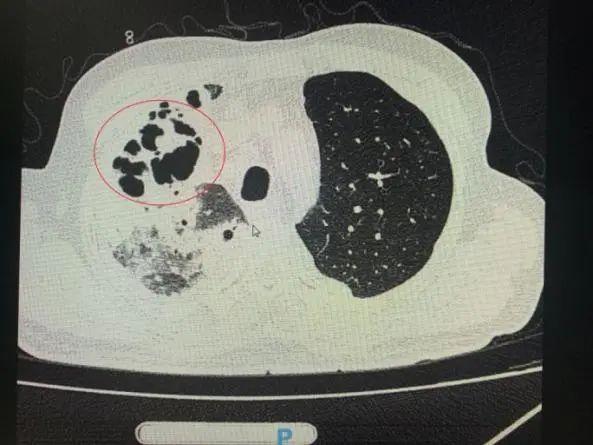

番禺院區(qū)呼吸內(nèi)科何夢璋主任接診后,對鐘叔進(jìn)行詳細(xì)檢查。此時,鐘叔的病情已經(jīng)十分危急,由于不能自主呼吸,他帶上了呼吸機(jī)輔助呼吸調(diào)節(jié)。看到鐘叔胸片時,醫(yī)護(hù)人員頭皮也一陣發(fā)麻,胸部CT可見雙肺多發(fā)的炎癥浸潤、雙肺多發(fā)空洞。通俗來說,鐘叔的肺部已經(jīng)被病原體蠶食,啃出個大小各異的洞!可怕的是,這種病變對肺功能的破壞是性、不可恢復(fù)的。根據(jù)鐘叔病史以及胸部CT結(jié)果,終診斷為“吸入性肺膿腫”。

鐘叔的肺部被病原體蠶食,啃出個大小各異的洞。